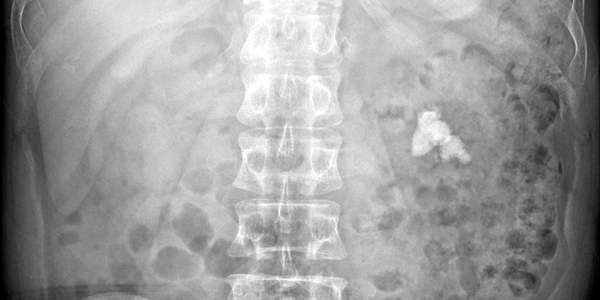

Sỏi thận ở bệnh nhân quan sát được qua phim X-Quang

Sỏi bệnh nhân quan sát qua Xquang được lấy ra khỏi cơ thể với vết mổ chưa đến 1 cm

Sau khi xác định tình trạng sỏi hiện tại của BN phù hợp để điều trị bằng tán sỏi qua da đường hầm nhỏ (mini – PCNL), phương pháp hiện đại nhất hiện nay trong việc điều trị sỏi thận, sỏi đường tiết niệu. Thông qua một đường hầm nhỏ 18Fr (tương đương 0,6 cm) được tạo từ hông lưng bệnh nhân vào thận, dưới sự dẫn đường của sóng siêu âm, tia Holmium laser (laser công suất lớn) sẽ tán nhỏ, làm sạch và đưa sỏi ra khỏi cơ thể trong một lần điều trị. Sau cuộc nội soi kéo dài 90 phút, bệnh nhân được chuyển về phòng hồi sức, tình trạng sức khỏe ổn định và xuất viện sau 3 ngày.